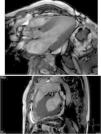

Cardiac magnetic resonance (CMR) showed marked concentric left ventricular (LV) hypertrophy, mild right ventricular (RV) hypertrophy and normal ejection fraction. There was biatrial enlargement, thickening of the interatrial septum and mild pericardial effusion (Figure 3). Short-tau inversion-recovery (STIR) sequences showed no myocardial edema or inflammation. In late gadolinium enhancement study, there was difficulty in setting the optimal inversion time to correctly null the myocardium, with a relatively dark blood pool and diffuse subendocardial enhancement of the interatrial septum and the LV and RV walls (Figure 4). The diffuse subendocardial late gadolinium enhancement, coupled with abnormal myocardial and blood-pool contrast kinetics, was most consistent with cardiac amyloidosis. The fact that the optimal inversion time that would null the normal myocardium could not be found is an indirect sign suggesting amyloidosis, because if abnormal fibrils are widespread in the intercellular space, the gadolinium may not be taken up by healthy myocardium.3

Cardiac magnetic resonance, 4-chamber view, depicting the late phase after gadolinium injection, with widespread subendocardial hyperenhancement of the left ventricle, not matching any coronary artery territory, but also involving the right ventricle, both atria and the interatrial septum.